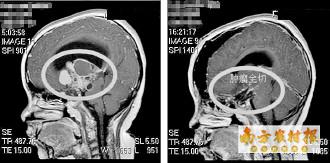

颅内巨大肿瘤完整切除。

近日,广东三九脑科医院副院长、神经外五科主任鲁明成功将小明颅内的巨大颅咽管瘤切除。

5月22日,鲁明为小明在全麻下行巨大颅咽管瘤切除术。术中发现肿瘤巨大,包裹了颈内动脉、大脑前动脉和中动脉,且肿瘤位于脑深部,钙化明显,质地坚韧,手术难度极大。经过手术团队近12个小时的奋战,才终于顺利将肿瘤切除。术后测量显示该颅咽管瘤大小约5cm×5.6cm×7.7cm厘米,比鸡蛋还大。目前小明恢复良好。